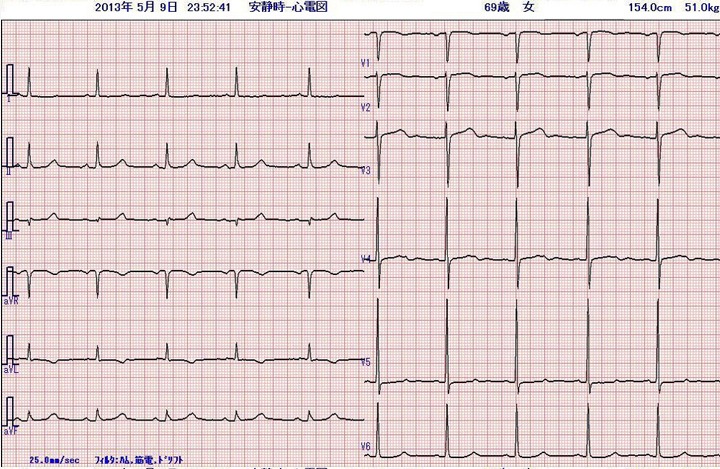

身体所見にその他、特記すべき異常所見はありません。その時にとられた心電図です。

これまで全く自覚症状のない人に左胸部痛が出現しています。吸気時に増強するという記載があり、非定型的ではありますが、まず急性冠症候群を考えます。冷汗と嘔吐という全身症状を伴っており、手術後の痛みや不安感だけでは説明できません。鑑別診断としては急性肺血栓塞栓症ですが、SpO2が正常であることから否定的です。緊急で施行した心エコー検査でも右室負荷の所見はみられませんでした。 心電図の所見は、Ⅰ、aVL、V4-6でT波の逆転、ないし平低化を認めます。術前にとられた心電図を示します。術前の心電図と比較すると、問題の心電図異常は新しく起きた変化であることが分かります。この所見からは、左室高位側壁、左室前壁から側壁にかけて心筋虚血がおこっている可能性があります。

術前心電図